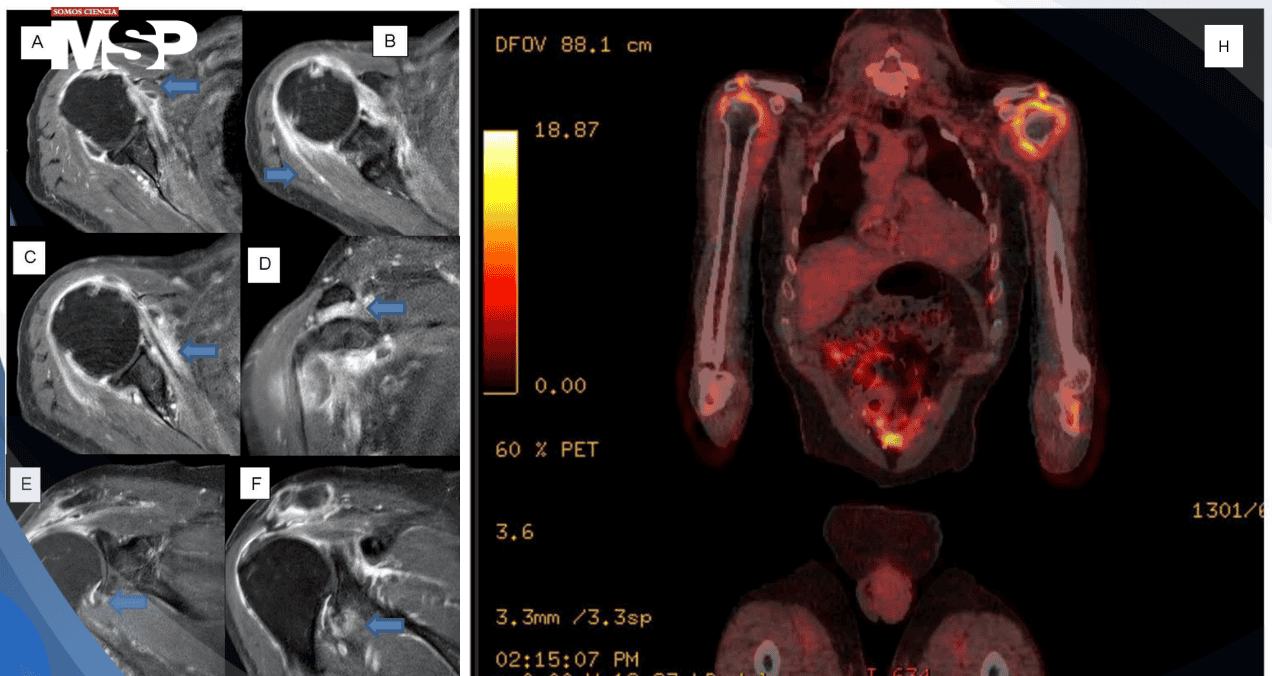

Dada la persistencia del dolor en hombros y la magnitud de la elevación de los marcadores inflamatorios, se realizó resonancia magnética de ambos hombros que demostró bursitis subacromial y subdeltoidea bilateral, sinovitis, capsulitis y peritendinitis, hallazgos característicos de PMR sin lesiones destructivas focales.

Para excluir definitivamente infección oculta, malignidad o vasculitis de grandes vasos, se realizó PET-CT con fluorodesoxiglucosa. Este estudio mostró captación aumentada de FDG en hombros y caderas de distribución simétrica periarticular, consistente con bursitis e inflamación, sin evidencia de lesiones nodales, viscerales, óseas focales, infección profunda o vasculitis de grandes vasos.

Con base en la presentación clínica característica (dolor bilateral de hombros y cintura pélvica, rigidez matutina prolongada en paciente mayor de 50 años), los marcadores inflamatorios marcadamente elevados, los hallazgos de resonancia magnética de hombros y el patrón de captación en PET-CT compatible con inflamación periarticular simétrica, se estableció el diagnóstico de polimialgia reumática.